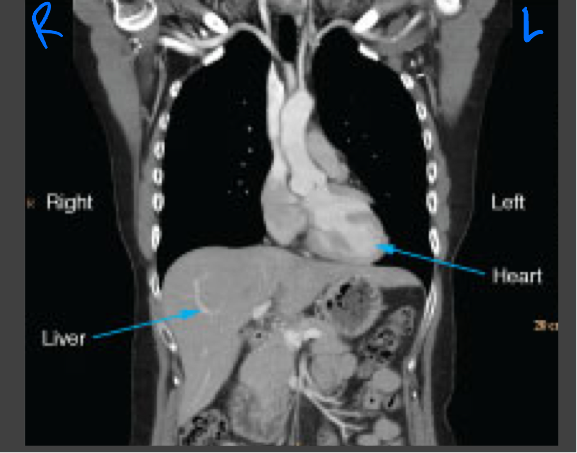

Coronal CT images

Viewed the same way that most radiographs are viewed: the images are oriented as though the patient is looking at you

Abdominal and pelvic CT

Evaluating the abdominal organs for pathology such as acute abdomen or trauma